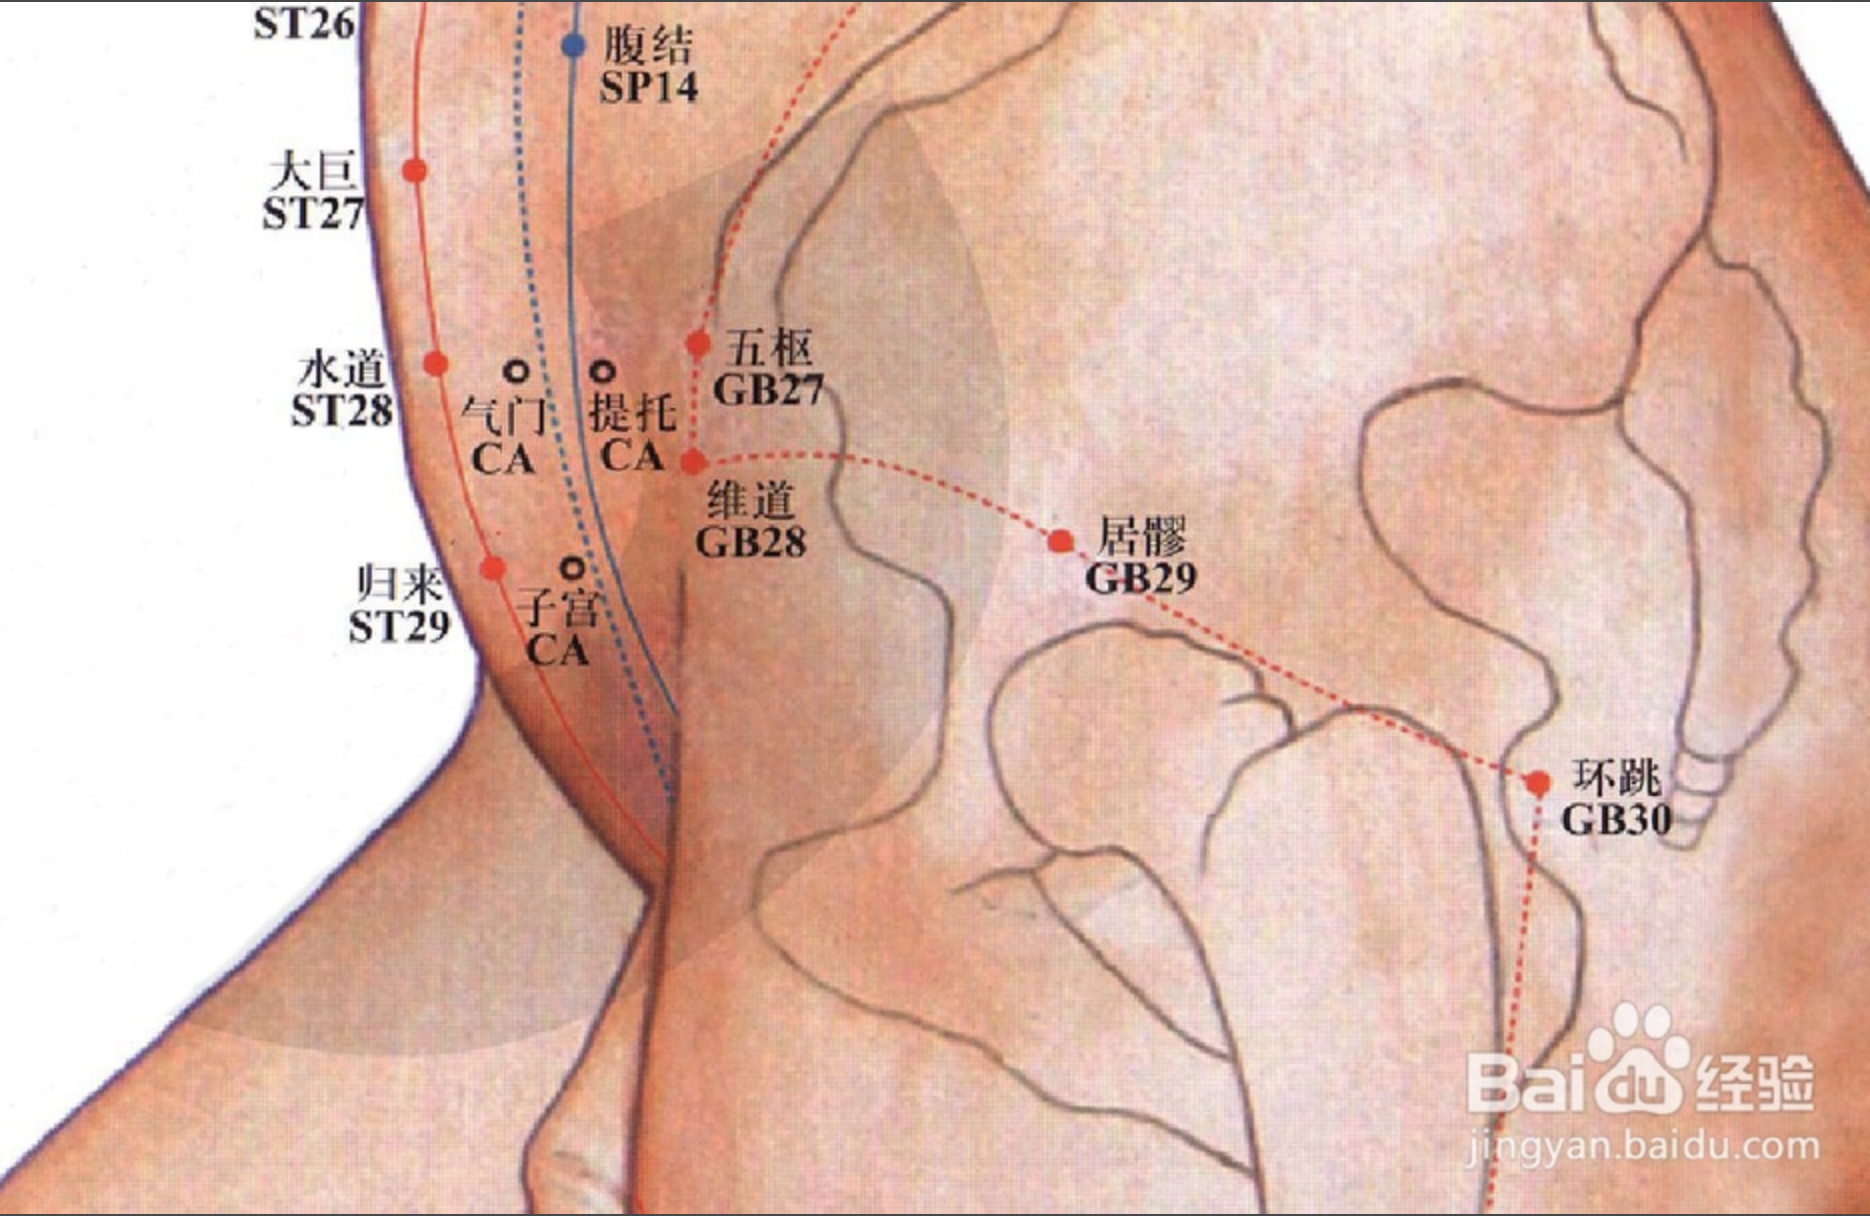

【(十一)足少阳胆经(图 10-29-1)】

2、歌诀 少阳足经瞳子髎,四十四穴行迢迢,听会上关颌厌集,悬颅悬厘曲鬓翘,率谷天冲浮白次,窍阴完骨本神邀,阳白临泣木窗辟,正营承灵脑空摇。风池肩井渊腋部,辄筋日月京门标,带脉五枢维道续,居髎环跳风市招,中渎阳关阳陵泉,阳交外邱光明宵,阳辅悬钟邱墟外,临泣地五会侠溪,第四指端窍阴毕。

3、经脉循行 起于目外眦(瞳子髎),向上到额角,返回下行至耳后,沿颈部向后交会大椎穴,再向前入缺盆部,入胸过膈,联络肝脏,属胆,沿胁肋部,出于腹股沟,经外阴毛际,横行入髋(kuān)关节(环跳)。

耳后支部:从耳后入耳中,出走耳前,到目外眦处向后向下经颊部会合前脉与缺盆部。下行腋部,沿侧胸部,经季肋和前脉会于髋关节后,再向下沿大腿外侧,行于足阳明和足太阳经之间,经腓(féi)骨前直下到外踝前,进入足第 4 趾外侧端(足窍明)。

足背部支脉:从足临泣处分出,沿第 1、2跖骨之间,至大趾端(大敦)与足厥阴经相接。

4、主要病候 口苦、目眩、疟疾、头痛、颌痛、目外眦痛、缺盆部、腋下、胸胁、股及下肢外侧、足外侧痛等。

5、主治概要 主治侧头、目、耳、咽喉病、神志病、热病及经脉循行部位的其他病证。

环跳

【定位】 在股外侧部,侧卧屈股,当股骨大转子最凸点与骶管裂孔连线的外 1/3 与中 1/3 交点处。

【主治】 腰胯疼痛,半身不遂,下肢痿痹,遍参风疹,挫闪腰痛,膝踝肿痛不能转侧。

【配伍】 配风市治风痹,配太白、足三里、阳陵泉、丰隆、飞扬治下肢水潴留、静脉炎,配风市、膝阳关、阳陵泉、丘墟治胆经型坐骨神经痛,配居髎、风市、中渎治股外侧皮神经炎,配髀关、伏兔、风市、犊鼻、足三里、阳陵泉、太冲、太溪治小儿麻痹、肌萎缩、中风半身不遂。

【刺灸法】 直刺 2 ~ 2.5 寸;可灸。

【附注】 足少阳、太阳二脉之会。